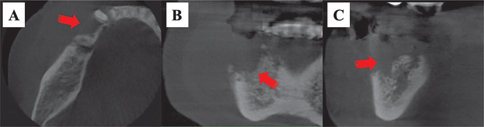

Fig 2

Figure 2. Cone beam computed tomography. Images showing extensive bone resorption and sequestration of osteoradionecrosis in the right mandibular premolar region (red arrows). A: axial; B: coronal; C: sagittal.